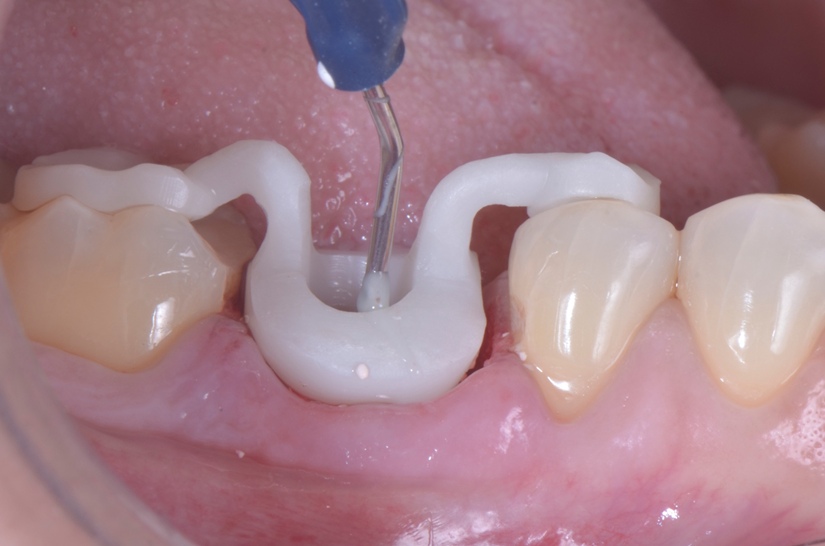

O paciente apresentou fratura vertical mésio-distal no elemento 46. Foi planejada a exodontia minimamente traumática e instalação imediata do implante Maestro Superiore (Implacil Osstem) utilizando uma guia prototipada. Após a exodontia, o implante foi instalado seguindo o protocolo de cirurgia guiada. O GAP vestibular foi preenchido com o Extra Graft. Um cicatrizador personalizado impresso com haletas facilitadoras foi capturado com resina flow e instalado. Após 30 dias, foi realizado escaneamento indireto para obtenção do perfil de emergência, utilizando protocolo digital com sobreposição do cicatrizador escaneado para confecção da coroa definitiva em zircônia policristalina estabilizada por ítria.

O uso de cicatrizadores personalizados, especialmente confeccionados por impressão 3D, tem ganhado destaque por permitir a conformação tecidual progressiva, facilitando a reprodução do perfil de emergência no fluxo digital6,7. A captura do cicatrizador com haletas de retenção com resina flow e seu posterior escaneamento são etapas críticas para assegurar a fidelidade da transferência do perfil de emergência e garantir um planejamento restaurador mais previsível8.

Neste caso, a sobreposição digital entre o cicatrizador escaneado e o desenho da coroa possibilitou comparar perfis de emergência com excelente adaptação clínica, contribuindo para um resultado estético e funcional adequado.